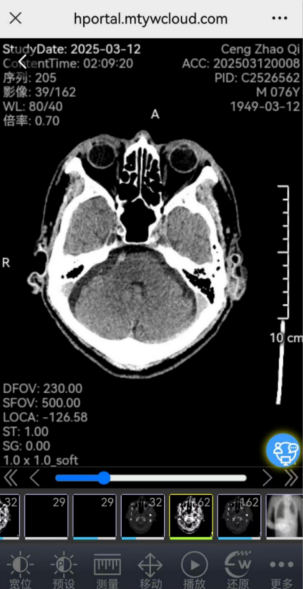

5“影像报告”如下图所示

影像云胶片系统的上线,彻底改变了这一局面。患者检查结束后,无需漫长等待胶片打印,只需通过手机、平板电脑等移动设备扫描专属二维码,即可随时随地查看高清影像。云胶片系统依托先进的云计算技术,将患者的影像资料以数字化形式安全存储在云端。患者可在线进行多种操作,如缩放、旋转、测量、三维重建等,细节一览无余,方便又快捷。